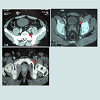

30 year-old male with no predisposing risk factors of venous thromboembolic disease; he has been diagnosed through a doppler ultrasound of a right iliofemoral-popliteal DVT. Consequently, thrombophilia and anti-cardiolipin antibodies analysis were carried out with a negative result. In the same way, a computed tomography and a phlebography identified a hypoplasia of inferior vena cava. After an early suspension of anticoagulation (withdrawn after a month by the patient himself), he presented, after eight years, another DVT in his iliofemoral vein and his left lumbar vein, which were diagnosed through an ultrasound scan and a computerized tomography, showing hypertrophy of the azygos and hemiazygos systems (Figures 1-3). After a physical examination, it was noted a secondary varicose veins in the abdomen constantly increasing when performing valsalva maneuvers (Figure 4). As a treatment, it was decided to perform indefinite anticoagulation with 4-hydroxycoumarins. After 5 years of evolvement, there is no post-thrombotic syndrome in the lower limbs although the abdominal varicose veins and collateral circulation persisted.Discussion